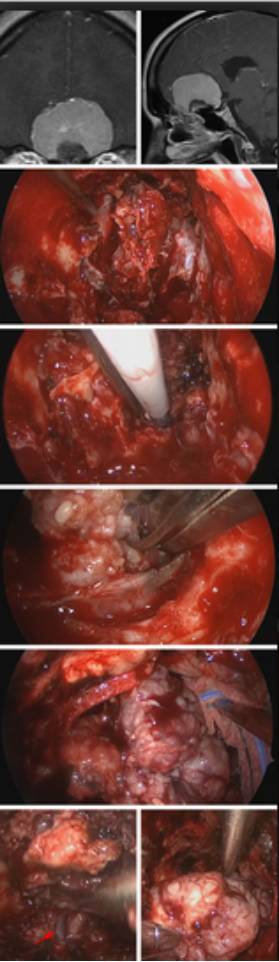

图12. 伴有筛骨骨质增生的巨大嗅沟脑膜瘤(第一排),肿瘤的横向范围没有超过眼眶的中线;部分蝶窦和全部筛窦已切除(第二排);切除筛骨眶板到达瘤体的外侧极。瘤性增生的骨质已被切除(第三排);肿瘤供血血管在镜下离断(第四排);肿瘤内减压后,肿瘤囊壁从受累的软脑膜上分开并垫上棉片(第五排);可见大脑前动脉(红色箭头所指),肿瘤最终被切除(最后一排)。